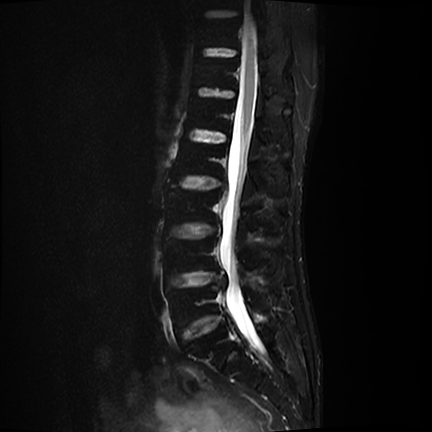

MRI提示L4/5椎间盘右侧突出明显

严重压迫神经根